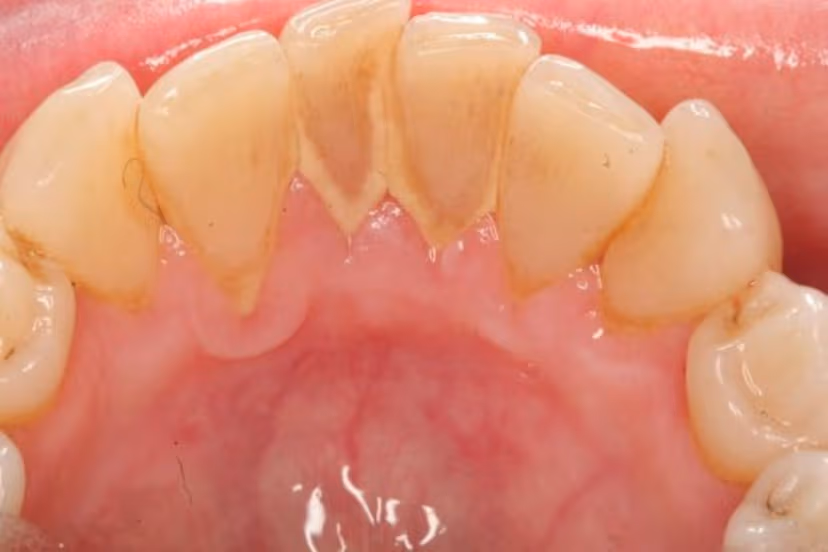

Cao răng, hay còn gọi là vôi răng, là một dạng vôi hóa mảng bám chứa vi khuẩn, thức ăn thừa, tế bào chết bám dính trên bề mặt răng và dưới nướu. Cao răng hình thành do quá trình khoáng hóa mảng bám mềm, nếu không được loại bỏ kịp thời có thể dẫn đến nhiều hậu quả nghiêm trọng cho sức khỏe răng miệng.

Cao răng hình thành từ quá trình vôi hóa mảng bám chứa vi khuẩn